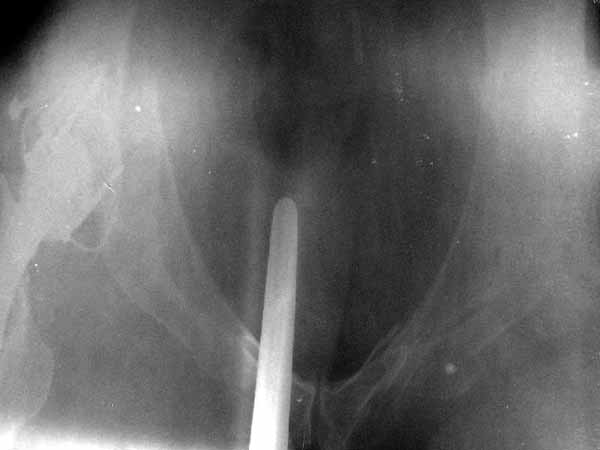

Dear All, A colleague of mine from another hospital requests opinion. A female 39 years old was operated ~1 year ago - right side THA for hypoplastic hip. Yesterday she was going to the hospital for THA of the second hip but got involved in a car accident. She admitted with right acetabular and left rami fractures (images attached). Also transverse fracture of the right distal femur. Seeking your advice regarding the acetabular fracture. THX!